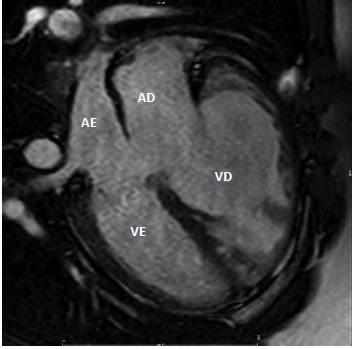

AD: átrio direito; AE: átrio esquerdo; VD: ventrículo direito; VE: ventrículo esquerdo

Na imagem de ressonância magnética cardíaca acima, a cardiopatia congênita que pode ser identificada é